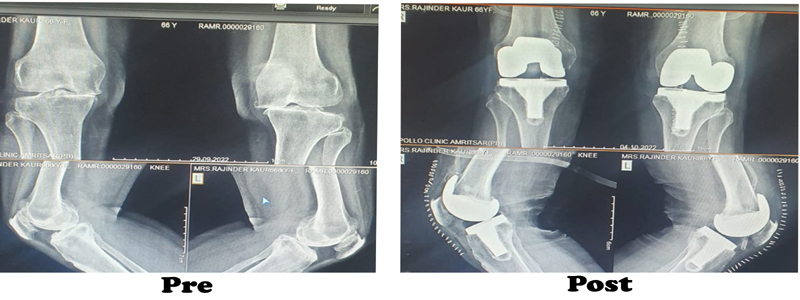

During the knee replacement surgery, the worn out surface (cartilage) of the joint is removed and is capped with implants called as endo-prosthesis. The femur and tibial sides are metal backed and in between there is polyethylene ‘insert’. The patella may or may not be replaced, depending upon the surgeon preference and condition of patellar cartilage.

The surgeon will make an incision on the top of your knee in order to expose the damaged area of your joint. The standard incision size can be as long as 10 inches, but a minimally invasive procedure can result in incisions as short as 6 inches. During the operation, the surgeon moves your kneecap aside and cuts away damaged bone and cartilage, which are then replaced with new metal and plastic components. The components combine to form a synthetic (but biologically compatible) joint that mimics the movement of your natural knee. Most knee replacement procedures take 30min - 1 hour to complete.

Recent advances in the form of minimal invasive (small cut) surgery, knees with high flex joints where one can still cross legs, joints that lasts longer, lesser blood loss, early recovery and holistic patient care, are the things which is offered to you by his team under his leadership.